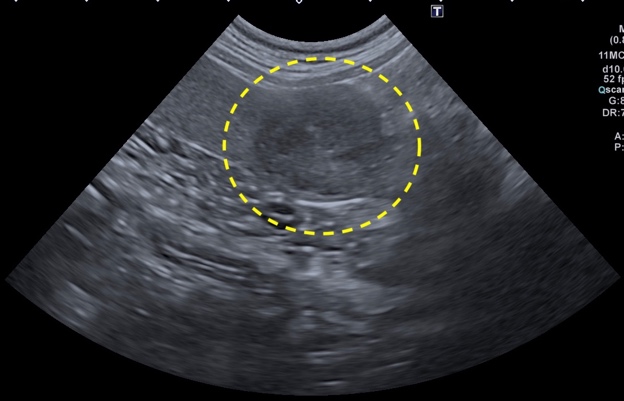

膀胱腫瘍

膀胱腫瘍は排尿がしづらくなったり、血尿や頻尿といった症状を示します。

膀胱腫瘍は犬で最も多い尿路系の腫瘍で、最も多いのは移行上皮癌である。腫瘍は膀胱三角領域に最も多く発生します。

腫瘍の発生部位により術式の選択が異なり、根治を目的とし拡大切除を行うこともある。また腫瘍により尿路が閉塞している場合は、閉塞の解除のための手術を行うこともあります。